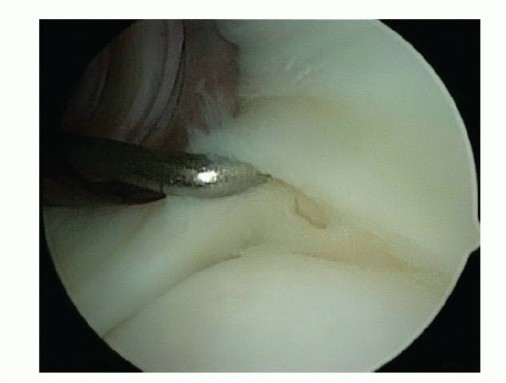

Arthroscopic Capsular Releases for Loss of Motion DEFINITION Shoulder stiffness can be a function of soft tis…